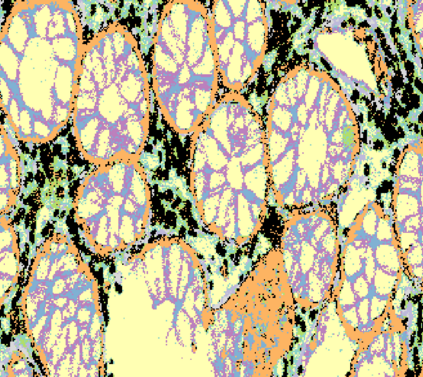

The usage of chemical imaging technologies is becoming a routine accompaniment to traditional methods in pathology. Significant technological advances have developed these next generation techniques to provide rich, spatially resolved, multidimensional chemical images. The rise of digital pathology has significantly enhanced the synergy of these imaging modalities with optical microscopy and immunohistochemistry, enhancing our understanding of the biological mechanisms and progression of diseases. Techniques such as imaging mass cytometry provide labelled multidimensional (multiplex) images of specific components used in conjunction with digital pathology techniques. These powerful techniques generate a wealth of high dimensional data that create significant challenges in data analysis. Unsupervised methods such as clustering are an attractive way to analyse these data, however, they require the selection of parameters such as the number of clusters. Here we propose a methodology to estimate the number of clusters in an automatic data-driven manner using a deep sparse autoencoder to embed the data into a lower dimensional space. We compute the density of regions in the embedded space, the majority of which are empty, enabling the high density regions to be detected as outliers and provide an estimate for the number of clusters. This framework provides a fully unsupervised and data-driven method to analyse multidimensional data. In this work we demonstrate our method using 45 multiplex imaging mass cytometry datasets. Moreover, our model is trained using only one of the datasets and the learned embedding is applied to the remaining 44 images providing an efficient process for data analysis. Finally, we demonstrate the high computational efficiency of our method which is two orders of magnitude faster than estimating via computing the sum squared distances as a function of cluster number.